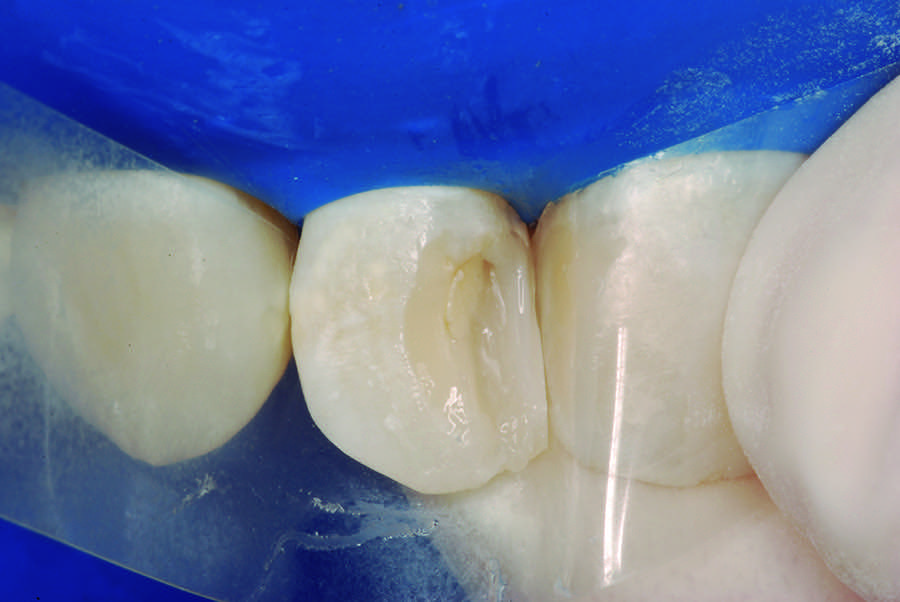

Once the maintenance of pulp vitality was verified, esthetic restorations of the teeth were performed. Initially, the teeth color shade was selected with the aid of a commonly used shade guide. After the isolation with a rubber dam, complete removal of the decayed dentin was performed in the teeth that received the stepwise excavation. The clinical verification of the presence of the mineralized barrier was performed in the maxillary lateral incisor with the aid of a disinfected gutta-percha cone, compatible with the diameter of the cavity. The authors recommend this procedure, because it allows the clinician to verify the formation of a mineralized barrier without compromising this critical area or causing a new exposure of the pulp tissue to the oral environment (Figure 11). After this, all teeth were treated with an indirect pulp capping technique. To obtain esthetics and functionality, beveling of both buccal and lingual surfaces was performed with No. 3118 diamond burs (Figure 12).

Fig 11. Clinical analysis of the mineralized barrier with a gutta-percha cone.

Figure 11